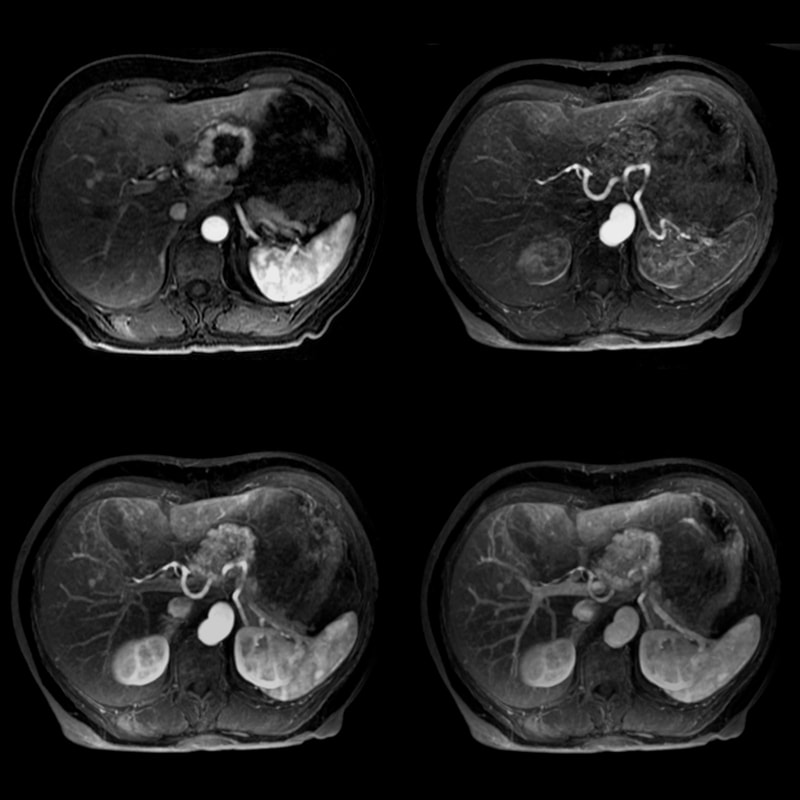

Методы динамического контрастирования печени на МРТ

Раздел: Снимки-подсказки